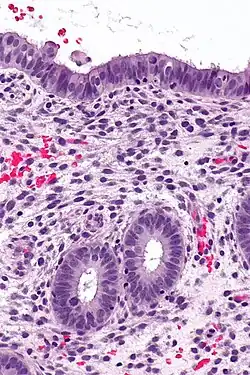

Histology of the most superficial layer of the endometrium, consisting of a simple columnar epithelium. H&E stain

The endometrium consists of a single layer of columnar epithelium plus the stroma on which it rests. The stroma is a layer of connective tissue that varies in thickness according to hormonal influences. In the uterus, simple tubular glands reach from the endometrial surface through to the base of the stroma, which also carries a rich blood supply provided by the spiral arteries. In women of reproductive age, two layers of endometrium can be distinguished. These two layers occur only in the endometrium lining the cavity of the uterus, and not in the lining of the fallopian tubes where a potentially life-threatening ectopic pregnancy may occur nearby.[4][5]